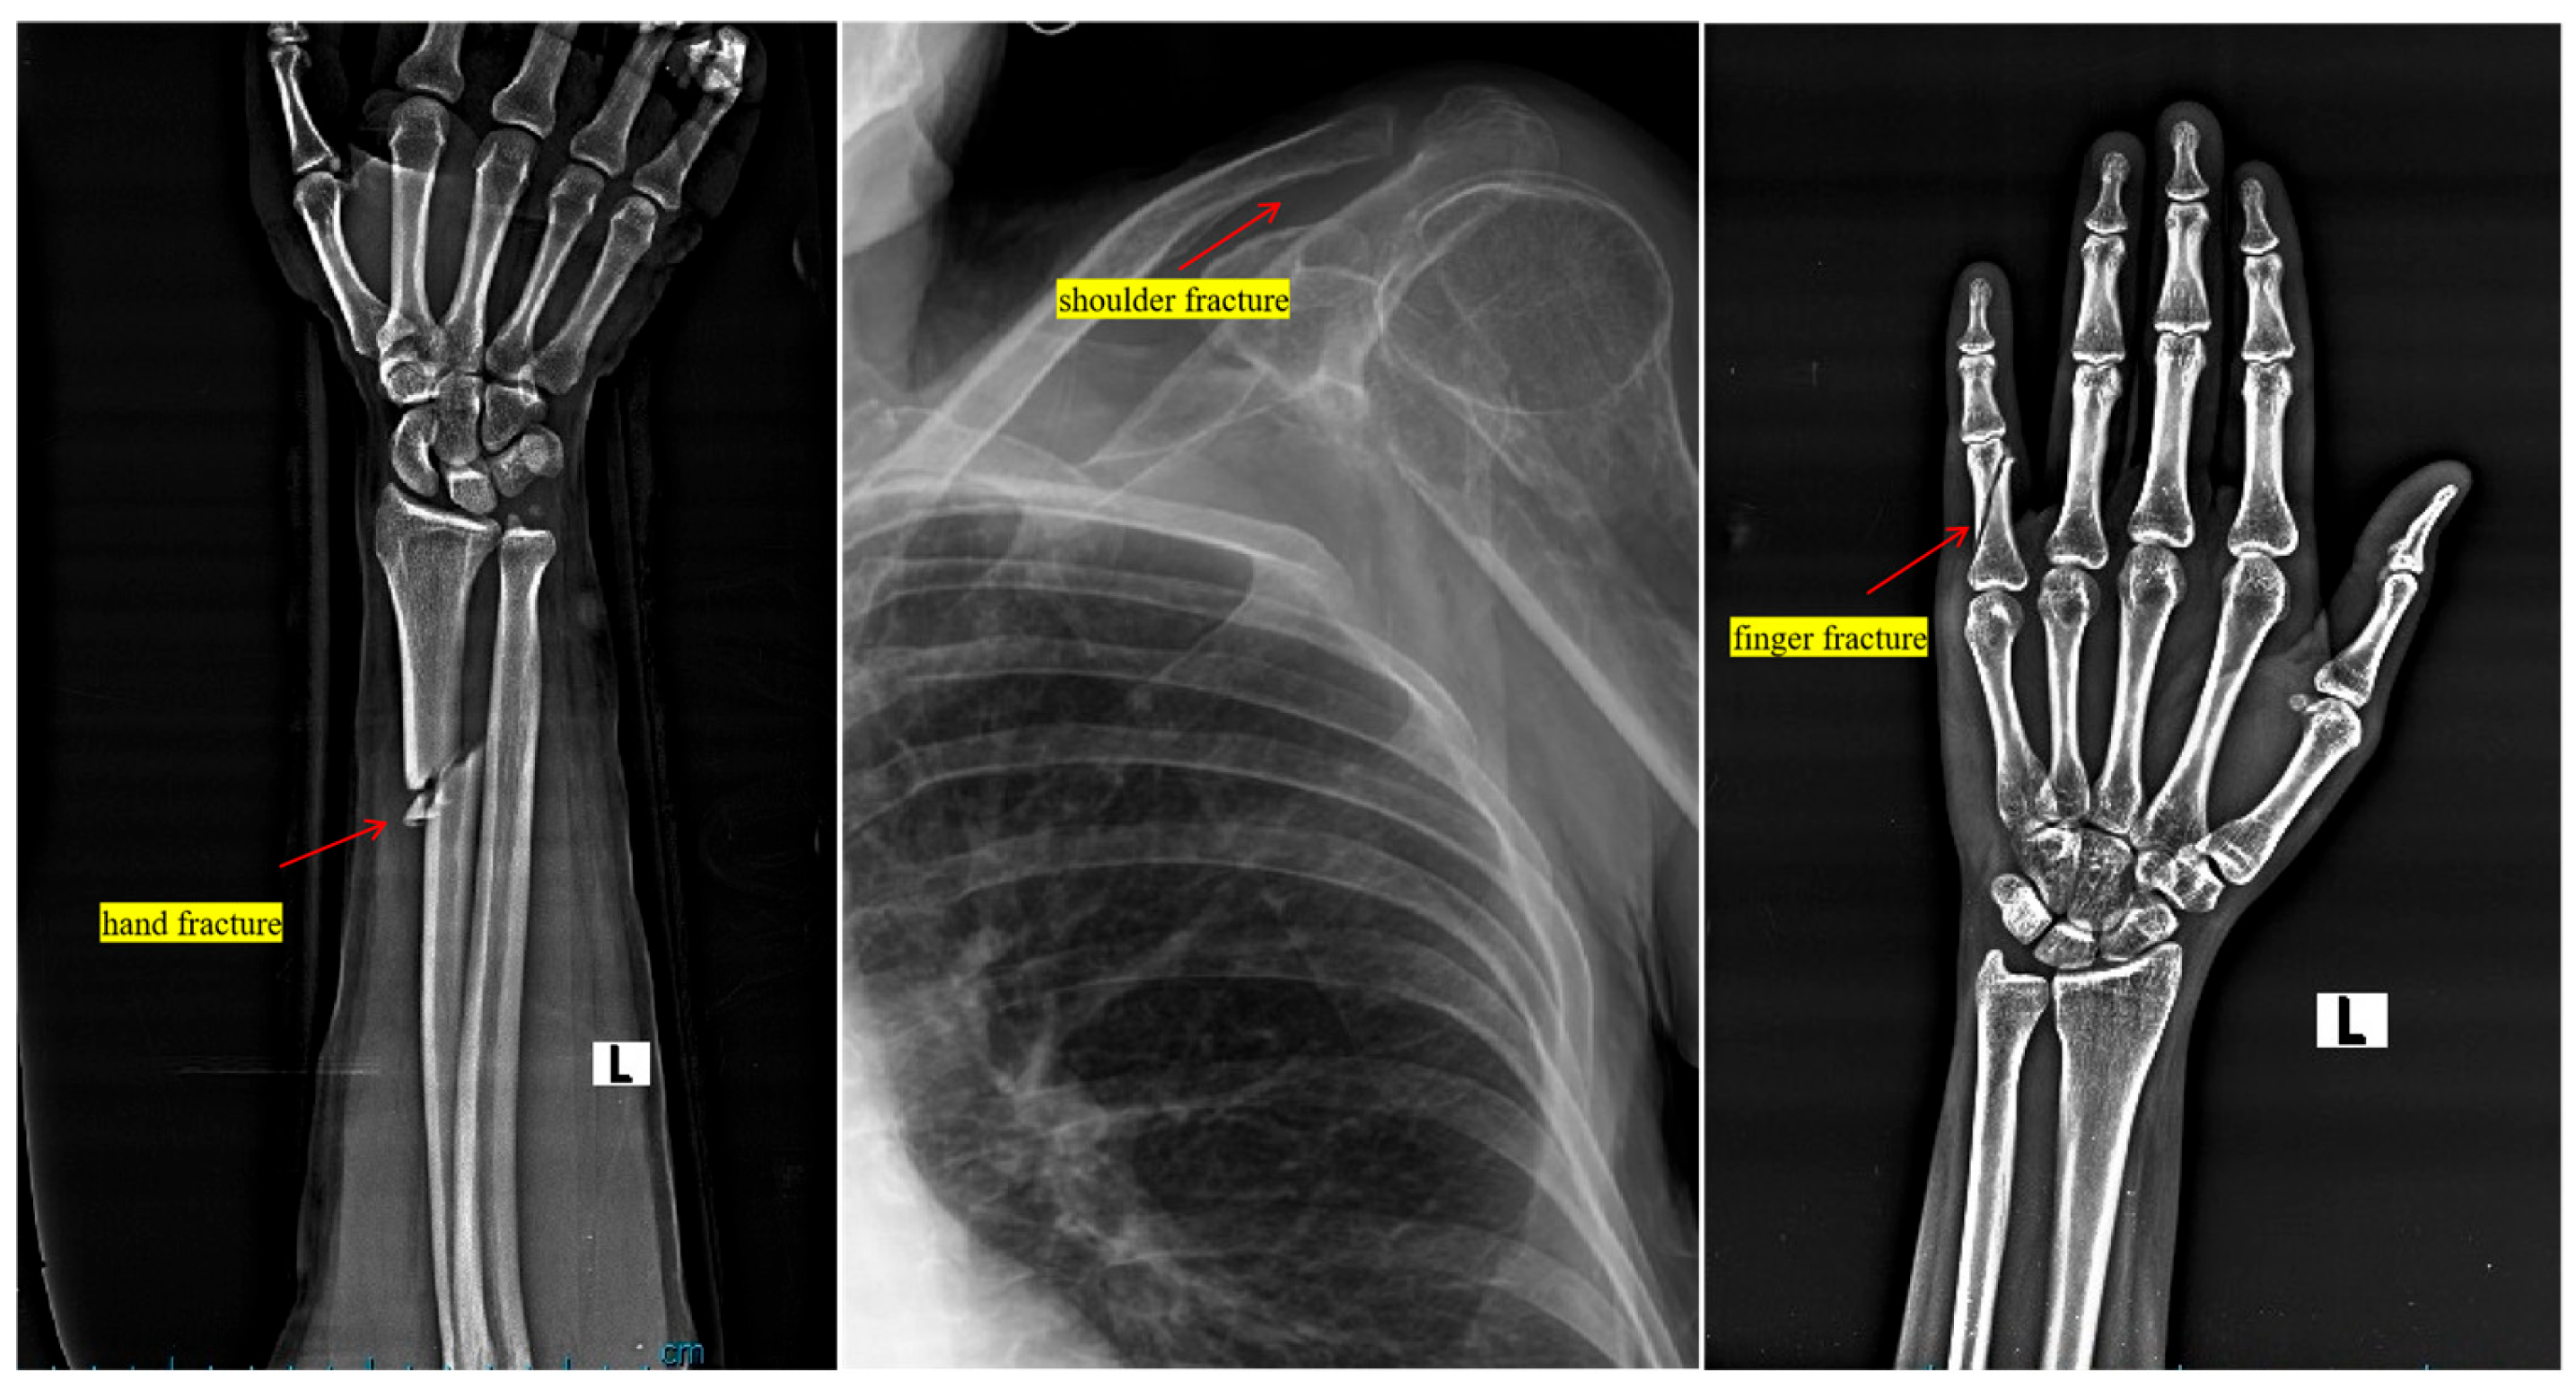

4.1. Dataset and Medical Image Preprocessing

- A custom-curated dataset focused on fractures prevalent among athletes was utilized, supported by preprocessing techniques like contrast enhancement and data augmentation, ensuring the robustness and generalizability of the model.